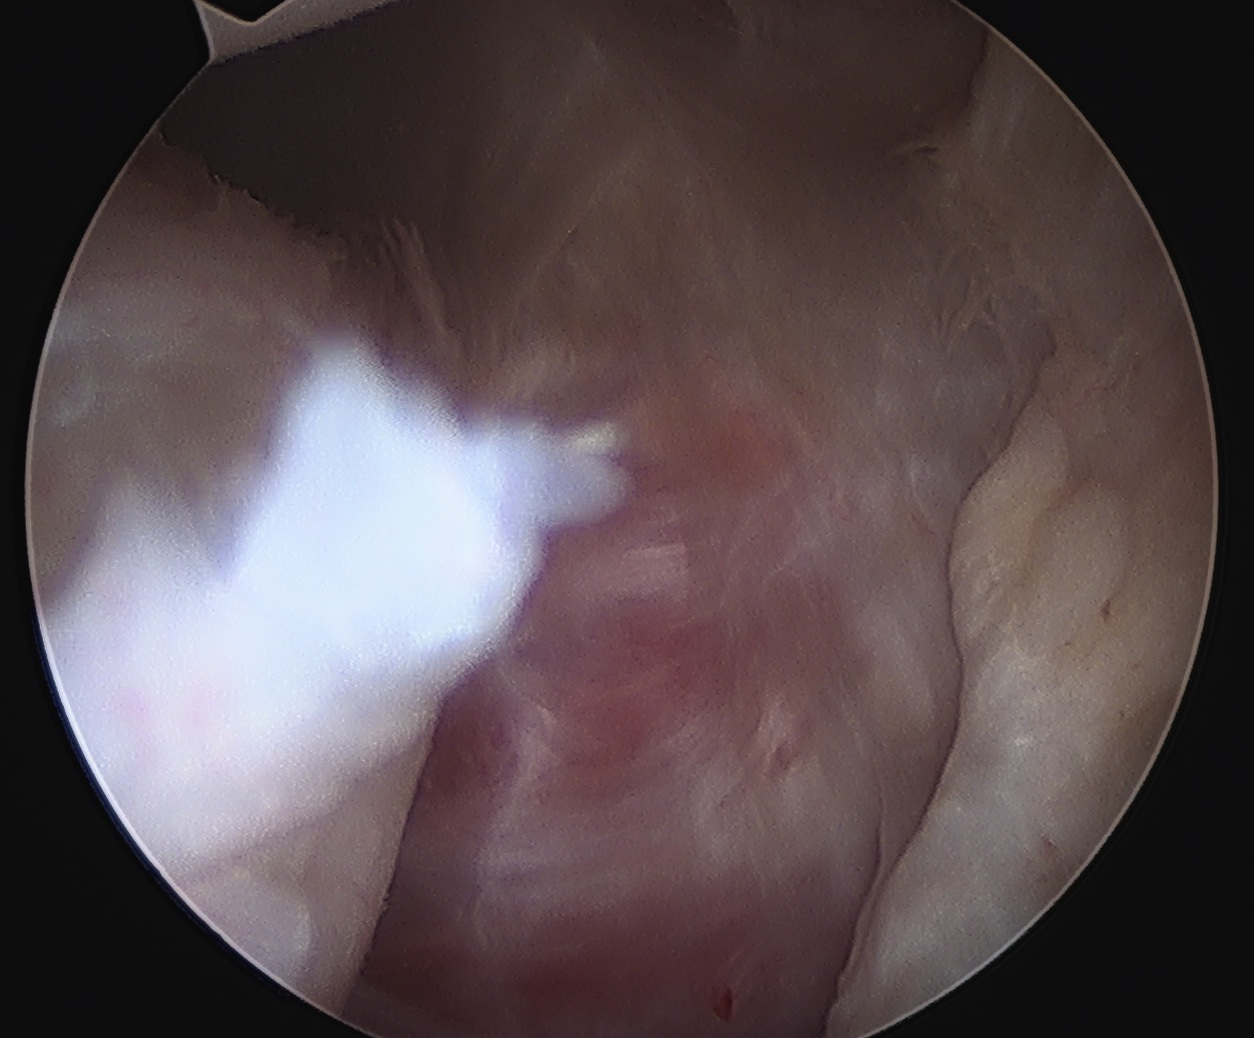

Arthroscopy

Capsule tear anteriorly, extending up into humeral insertion

Side to side repair of capsular tear

Intact anterior labrum with capsular tear, axillary nerve seen below capsular tear in axillary recess